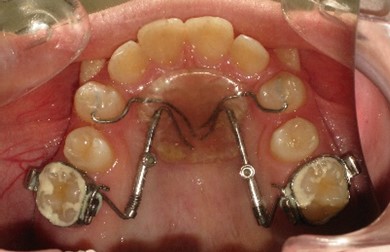

В плане ортодонтического лечения необходимо провести дистализацию боковых сегментов на верхней челюсти с постановкой моляров по нейтральному типу с последующей нормализацией формы зубных рядов на обеих челюстях и окклюзии. Первый этап лечения проводится с помощью несъемного дистализирующего аппарата – Distal Jet. (рис.4)

Данная конструкция ортодонтического аппарата выбрана обьективно, учитывая возраст пациента и незрелость костной ткани альвеолярного отростка на данном этапе формирования прикуса постоянных зубов. В более позднем возрасте целесообразно применение ортодонтических миниимплантатов с целью анкоража для дистализации боковых сегментов на верхней челюсти с постановкой моляров по нейтральному типу. Период дистализации первых моляров верхней челюсти с помощью аппарата Distal Jet занял примерно 5 мес. Отмечается корпусное перемещение моляров без изменения их осевого наклона в сагиттальном направлении, что дают конструктивные особенности аппарата Distal Jet с соответствующей силовой нагрузкой пружины NiTi . (рис.5)

Рис.4. Аппарат Distal Jet в полости рта на начальном этапе дистализации.